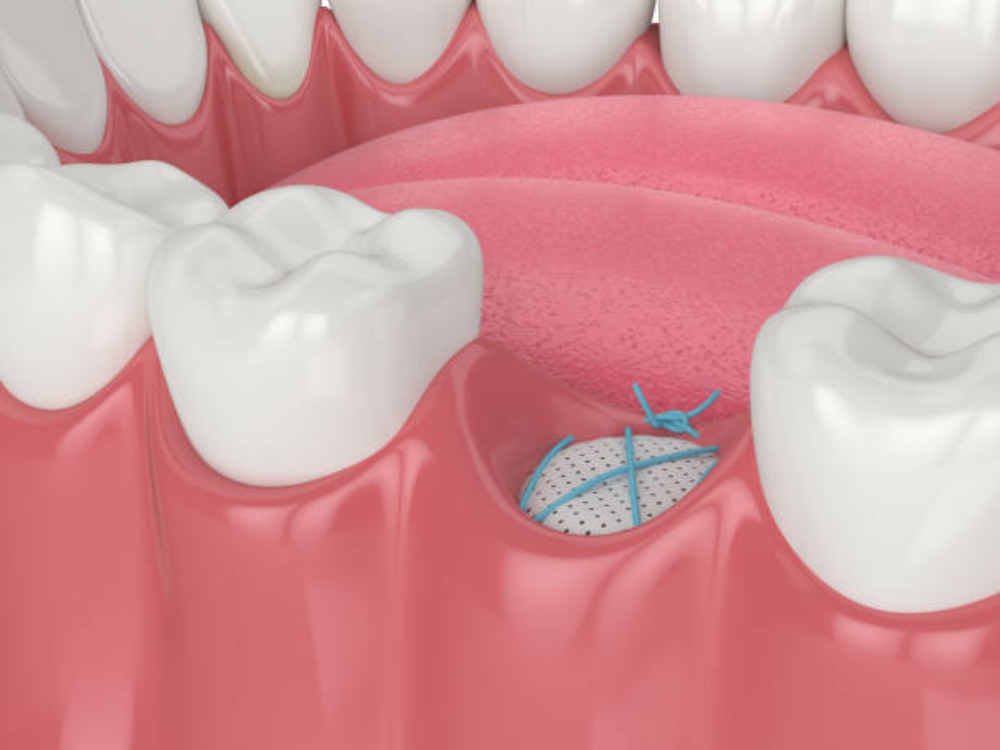

Regeneration Membrane – $350

Regeneration membranes are specialized barriers used during bone grafting procedures to guide new bone formation and prevent soft tissue interference. These biocompatible materials create a protected space for bone regeneration while excluding unwanted tissue growth. Our membranes help ensure successful bone grafting outcomes, improving implant success rates in challenging cases.

Bone Graft – $700

Bone grafting procedures rebuild insufficient jawbone to support dental implants successfully. Using advanced grafting materials and techniques, we can restore bone height, width, and density in areas affected by tooth loss, infection, or trauma. Our bone grafts may use synthetic materials, processed donor bone, or your own bone, depending on your specific needs and the extent of reconstruction required.

When necessary, we perform bone grafting, sinus lifts, or extractions to establish the ideal foundation for implant placement. These procedures may be completed in advance or combined with your implant surgery, depending on your case.

A: Many patients who have been told they’re not implant candidates can actually receive implants with bone grafting or sinus lift procedures. Our advanced 3D imaging allows us to assess your bone condition precisely and determine the best approach for your case. We offer various bone regeneration techniques including ridge augmentation, block grafts, and sinus lifts that can rebuild the foundation needed for successful implants. Even patients with significant bone loss often become excellent candidates after preparatory procedures. A thorough evaluation will determine your specific options.